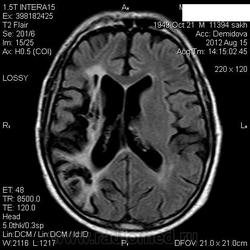

Мои собственные наблюдения.

1 случай -локальная гемиатрофия.2 случай-диффузная.

Молодой человек после автомобильной аварии.3 года лежит.Двигаются только глаза.Зрелище душещипательное.

Евгений, конечно же, мои случаи не являются "чистой" атрофией-согласна.Мне пока не встречались случаи болезни Пика, Альцгеймера и другие "чистой воды" атрофии.Второй случай- состояние после длительной комы вследствие автодорожной травмы 3 года назад.Пациент проходил исследование в прошлом году , в этом родители привезли на динамику.